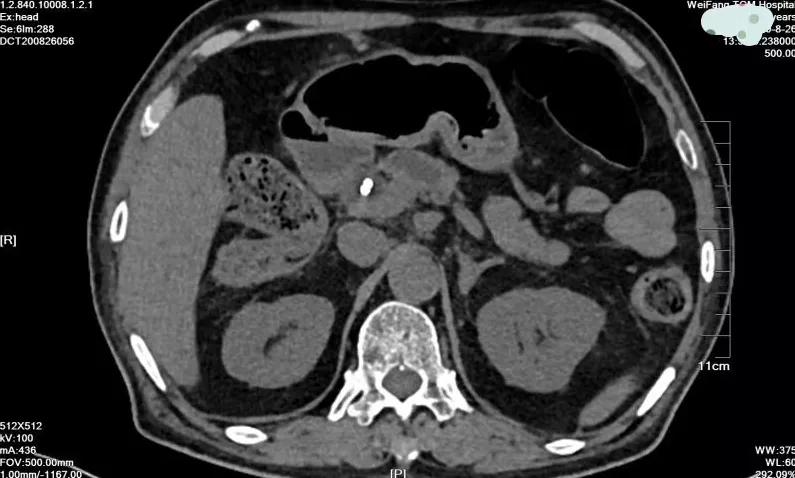

患者两年前因十二指肠乳头恶性肿瘤于外院放置金属胆管支架,普外科付云强主任根据其临床表现、血化验结果及影像学检查,初步诊断为术后肿瘤复发,除了有原胆道金属支架堵塞的情况外,还有新的情况,即胰管堵塞的情况,这是老人腹痛的根本原因。

8月28日,在麻醉科等科室的全力配合下,普外科付云强为主任为患者实施手术,术中付云强主任将十二指肠镜经口腔进入十二指肠,在十二指肠主乳头的方寸之间,细心的寻找胰管开口,功夫不负有心人,在其精湛的技术下,顺利的找到并放置了胰管支架,再经十二指肠乳头开口处注入造影剂行胆管造影,造影显示胆总管全程有充盈缺损,考虑肿瘤胆道系统广泛转移,术中诊断为壶腹部癌ERCP术后,胆总管及肝内转移。根据治疗计划行十二指肠逆行胰胆管造影术+原胆道支架拔除+胆道清理+胆道支架内引流术。手术顺利,术后患者安返病房。